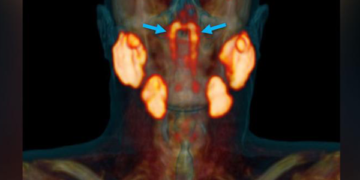

Read moreঅনলাইন ডেস্ক বহু শতাব্দীর গবেষণার পরও মানবদেহে এমন একটি অঙ্গ যে রয়েছে, যা এতদিন চিকিৎসকদের নজরে আসেনি। তবে নেদারল্যান্ডসের...